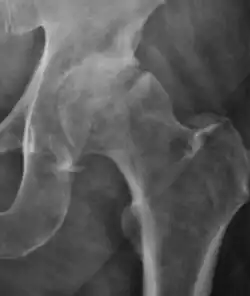

Plain radiography allows us to categorize the hip as normal or dysplastic or with impingement signs (pincer, cam, or a combination of both). Besides these, pathologic processes like osteoarthritis, inflammatory diseases, infection, or tumors can also be identified (Figure 1).[1]

Figure 1.

-

Radiography in normal hip -

X-ray in pincer impingement type of hip dysplasia -

X-ray of cam -

Hip in osteoarthritis -

Septic arthritis